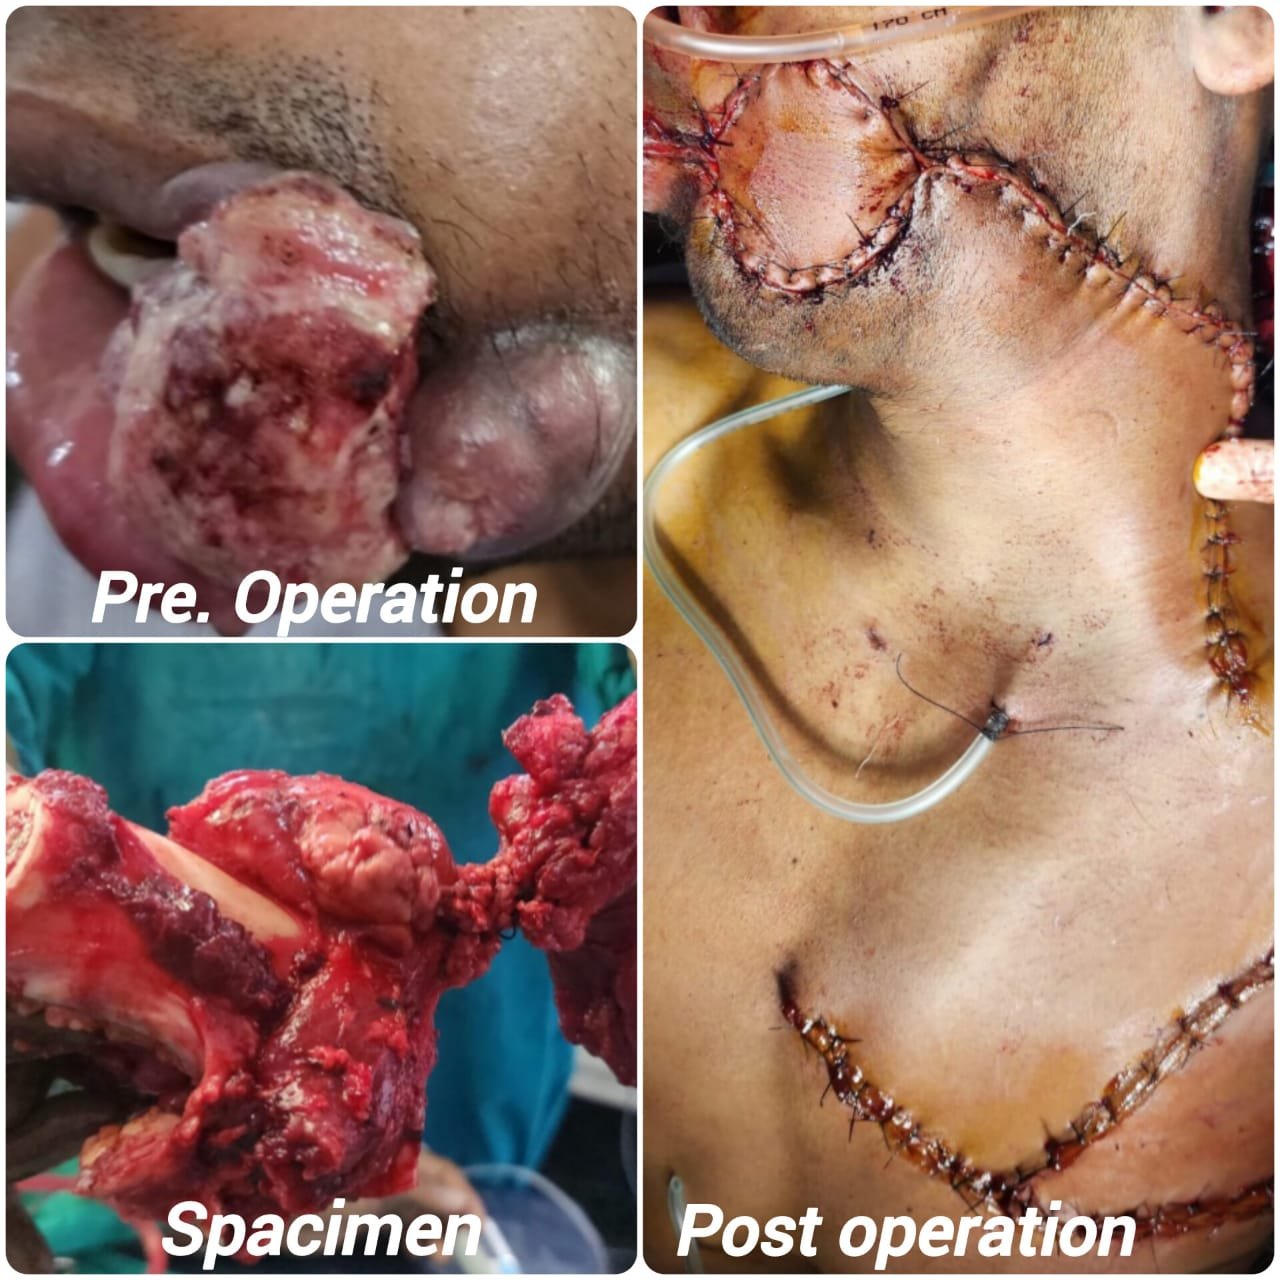

▶ गर्भाशय के कैंसर का उपचार एवं सर्जरी

Rana Hospital offers advanced care in Maternity, Gynecology, ENT, and Cancer Surgery. Our expert doctors provide personalized treatment with modern technology. We are committed to your family’s health, comfort, and speedy recovery.